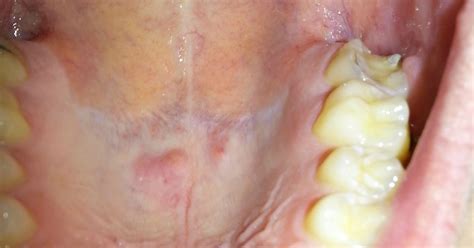

What Causes Sores and Bumps in the Mouth?